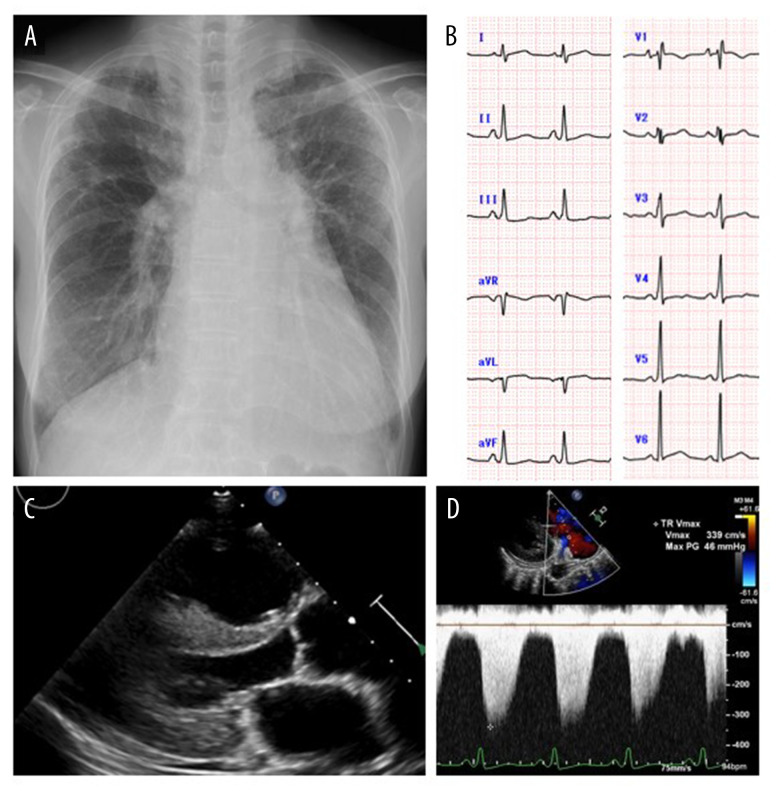

BACKGROUND Thiamine deficiency often occurs in patients with alcohol abuse and unbalanced diets. However, gastric surgery and/or use of diuretics can also cause this situation. Importantly, thiamine deficiency can cause pulmonary hypertension, which is completely reversible. This report is of a case of a 67-year-old woman who presented with pulmonary hypertension and thiamine deficiency following partial gastrectomy and exacerbated by diuretics. CASE REPORT A 67-year-old woman with histories of partial gastrectomy because of non-Hodgkin lymphoma (at age 36 years) and sigmoid colectomy because of colon cancer (at age 58 years) presented with bilateral leg edema and dyspnea on exertion. Electrocardiography and right heart catheterization revealed pulmonary hypertension. Despite diuretic administration (initially indapamide, then changed to torsemide), the symptoms gradually worsened. Although she was neither an alcohol drinker nor a fussy eater, we found that her blood thiamine concentration was extremely low. We diagnosed her as having thiamine deficiency caused by gastrectomy and administered diuretics. After intravenous thiamine administration, her symptoms showed immediate improvement, associated with the normalization of the pulmonary hypertension. After detailed analysis of the cause of her pulmonary hypertension, including Swan-Ganz catheterization and echocardiography, we concluded that her pulmonary hypertension was caused by thiamine deficiency following partial gastrectomy and exacerbated by diuretics. CONCLUSIONS This case highlights the importance of recognizing that thiamine deficiency can be a cause of pulmonary hypertension, and that thiamine deficiency can be associated with gastrectomy and the use of diuretics.